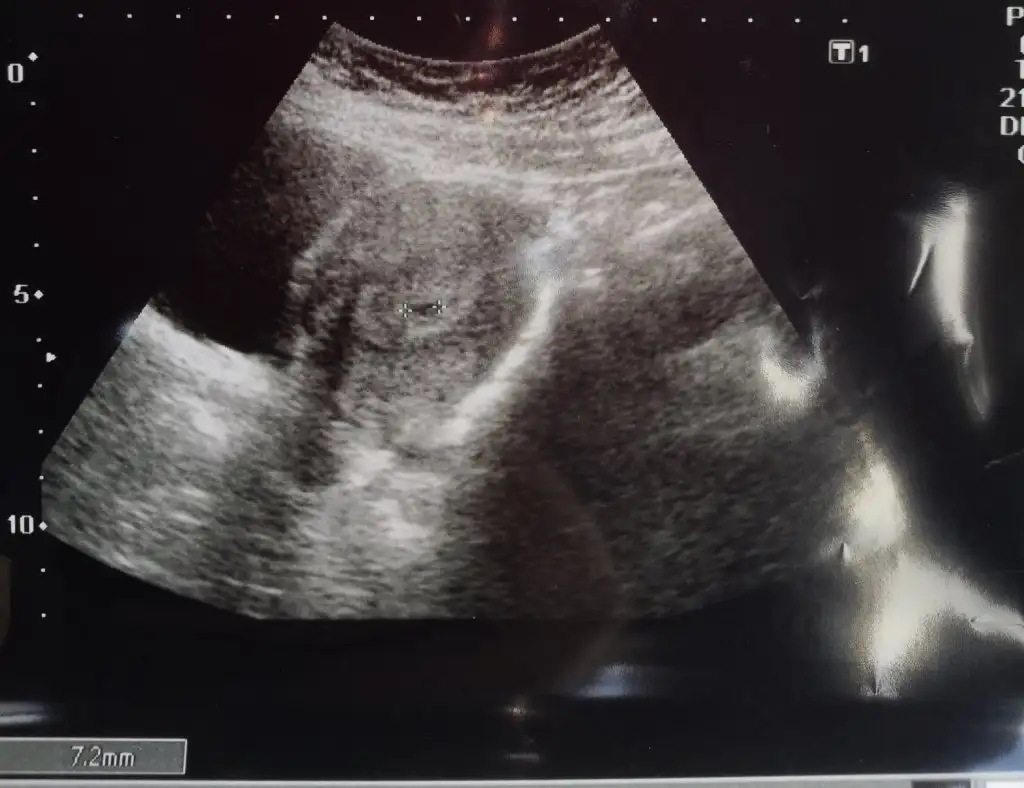

Selam arkadaşlar bugün ilk doktor kontrolüme gittim karından baktı kesemiz gözüktü 7.2mm satla uyumlu 5 haftalık2 hafta sonra kalp atışını duyarız dedi karından anca o zaman gözüküyor şimdi bekle bakalım 2 hafta kese sağlıklı normal gözüküyor dedi bir takım tahliller istedi onları pazartesi devlette yaptıracağım. Folik asite devam dedi, kanama falan durumunda haberim olsun dedi bir şikayetin yoksa 2 hafta sonra görüşürüz dedi bizden haberler böyle bekleyenler de en kısa zamanda mutlu haberleri alırlar inşallah